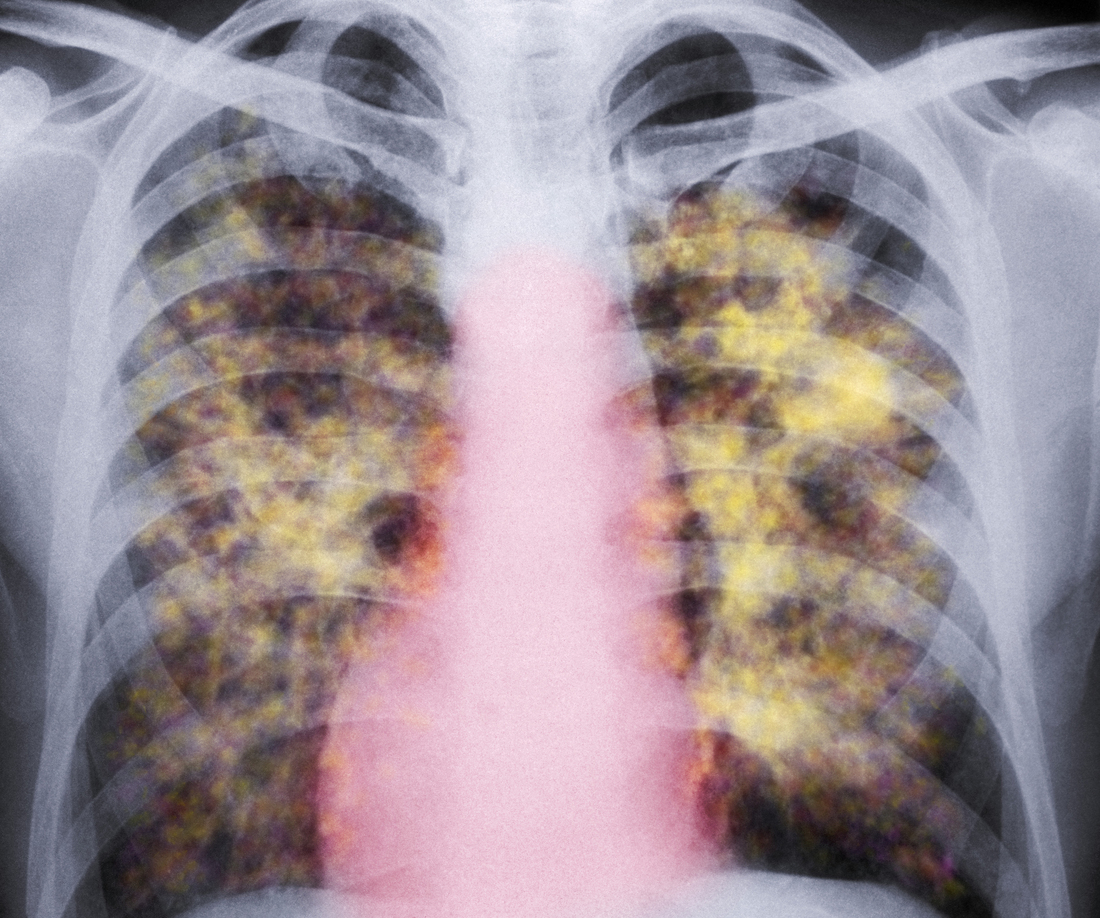

A colored X-ray of the lungs of a patient with silicosis, a type of pneumoconiosis. The yellow grainy masses in the lungs are areas of scarred tissue and inflammation.

CNRI/Science Photo Library/Getty Images